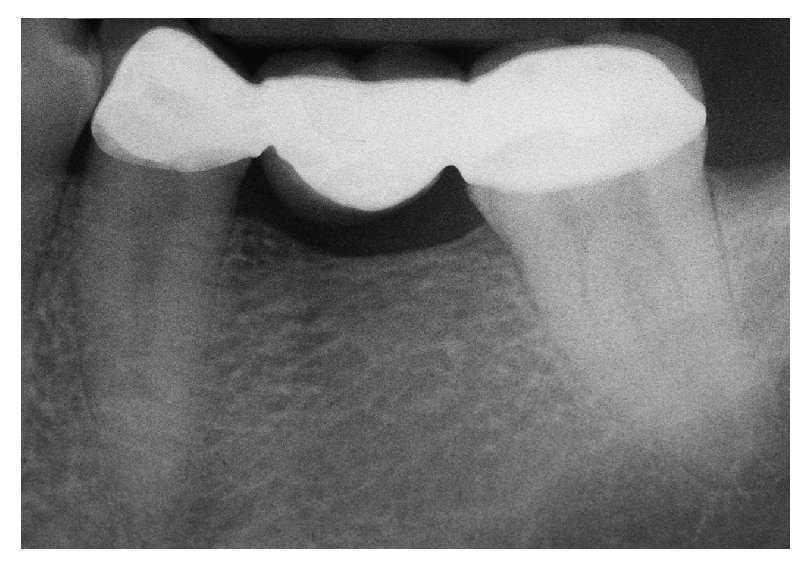

La paciente de 62 años se quejaba de dolores en el diente 36 al masticar. La anamnesis arrojó resultados normales. En la radiografía se apreciaba una fractura del diente (fig. 5a). Tras la extracción y el aumento óseo, la paciente deseaba la reposición del diente ausente mediante una corona individual implantosoportada, pero en ningún caso quería una prótesis extraíble.

Fig. 5a. Diente 34 con fractura radicular y pronóstico infausto.